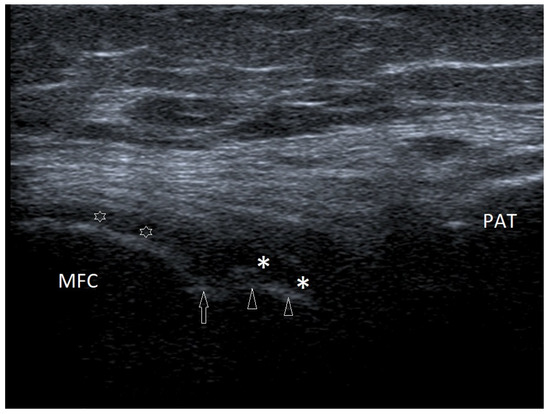

3.2.1. Osteochondritis Dissecans

3.2.6. Exudates and Inflammations Affecting Joints